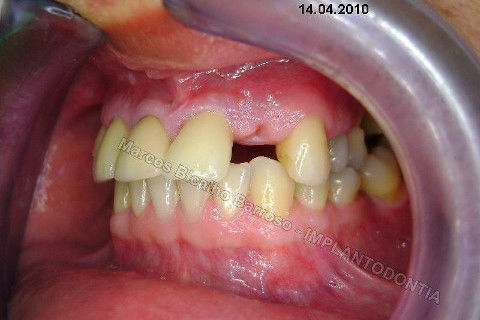

Este caso tem o objetivo de demonstração da técnica que normalmente sigo ; em casos onde ocorre fratura da raiz e consequentemente abscessos, com ou sem formação de fístula. Neste caso fiz a exodontia com preenchimento do alvéolo com biomaterial (osso bovino liofilizado + coágulo do paciente). Após 90 dias, mais ou menos, instalei o implante. Esperei mais 4 meses e realizei ontem (12/11/2010) a instalação do cicatrizador com o cuidado de preservar tecido mole, sem remoção de material, apenas afastando gengiva e "enrolando" a sobra de mucosa em direção a face vestibular, para promover conservação de papila futuramente. Se ocorrer excesso de papila, sem problema, remove-se um pouco, mas a intenção é não deixar faltar, o que resultaria em indicação para enxertos gengivais.